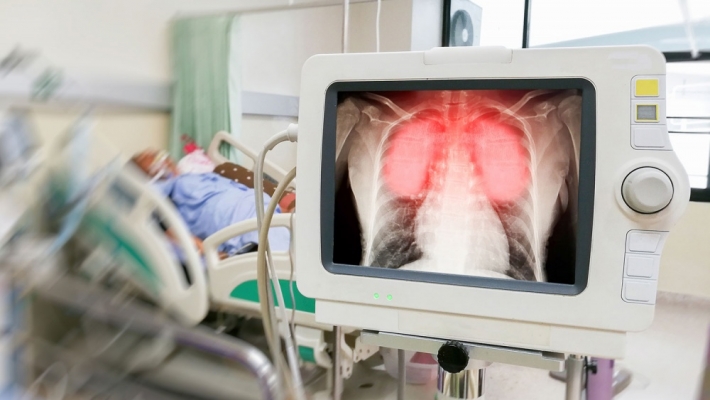

- Сегодня мы потеряли двух жителей Ульяновской области из Карсунского района. Первичные тесты оказались положительными. С большой долей вероятности они оба были заражены этой новой болезнью. Оба были госпитализированы с пневмонией в инфекционное отделение ЦГКБ Ульяновска, где получали интенсивную терапию и все необходимое лечение. Последние сутки пациенты были подключены к аппаратам ИВЛ. К сожалению, спасти этих людей, несмотря на все старания медиков, не удалось. Обоим больным было больше 65 лет. У одного на фоне коронавируса и хронического диабета развился инсульт, у второго - остановилось сердце. Это настоящая трагедия для нас. К сожалению, коронавирус действительно страшен людям в преклонном возрасте. Тем более если у них есть хронические заболевания. Но от осознания этого нисколько не легче. Несмотря на то, что эти трагичные случаи не имеют отношения к оказанию медицинской помощи в Карсунском районе, я могу заверить, что оба пациента получали все необходимое лечение в городской больнице, - заявил губернатор.

По информации регионального минздрава, 13 апреля в Центральную городскую клиническую больницу Ульяновска был госпитализирован с подозрением на коронавирусную инфекцию 67-летний житель Карсунского района. На фоне сахарного диабета у мужчины возникло острое нарушение мозгового кровообращения, состояние резко ухудшилось. Через два дня ночью пациент был подключён к аппарату искусственной вентиляции лёгких. Но несмотря на все усилия медиков, спасти жизнь пациента не удалось.

Еще один мужчина 65 лет из села Белозерье Карсунского района был госпитализирован в ЦГКБ с подозрением на новую инфекцию 14 апреля в тяжёлом состоянии с признаками острой дыхательной недостаточности. Пациенту была диагностирована двухсторонняя пневмония. Он был сразу подключён к аппарату ИВЛ. Ночью с 15 на 16 апреля произошла остановка сердца. Несмотря на проведение реанимационных мероприятий, спасти жизнь пациента не удалось.

Как сообщает министр здравоохранения Виктор Мишарин, на данный момент у обоих пациентов не подтверждён диагноз "коронавирусная инфекция". Однако весь круг контактных лиц данных пациентов установлен, все они находятся под наблюдением врачей. По словам главы ведомства, еще одна пациентка из Карсунского района умерла от пневмонии. Она заболела 30 марта, за медпомощью не обращалась, лечилась самостоятельно. 15 апреля она почувствовала себя гораздо хуже и обратилась в лечебное учреждение района, где в приемном отделении больную осмотрели, выполнили рентгенографию грудной клетки. Женщине был поставлен диагноз "двухсторонняя пневмония". В процессе оказания медицинской помощи наступила внезапная остановка сердечной деятельности. Ей начали оказывать реанимационные мероприятия, но они к успеху не привели, и через 30 минут была констатирована смерть больной.